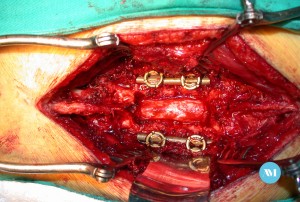

La lesión medular implica siempre una lesión traumática en la estructura músculo esquelética, ósea y en los ligamentos.

También pueden ocurrir lesiones directas, como cortaduras, particularmente si los huesos o los discos se debilitaron. Los fragmentos óseos (por ejemplo, los que provienen de fracturas en las vértebras, que son los huesos de la columna) o de metales (como los provenientes de un accidente de tránsito o herida de bala) pueden cortar o dañar la médula espinal.

Las lesiones en la primera vértebra lumbar y por debajo de esta no ocasionan lesión en la médula espinal. Sin embargo, pueden causar el «síndrome de la cola de caballo», una lesión en las raíces nerviosas de esta área. Este tipo de lesión de la médula espinal es una emergencia médica y necesita cirugía inmediata.